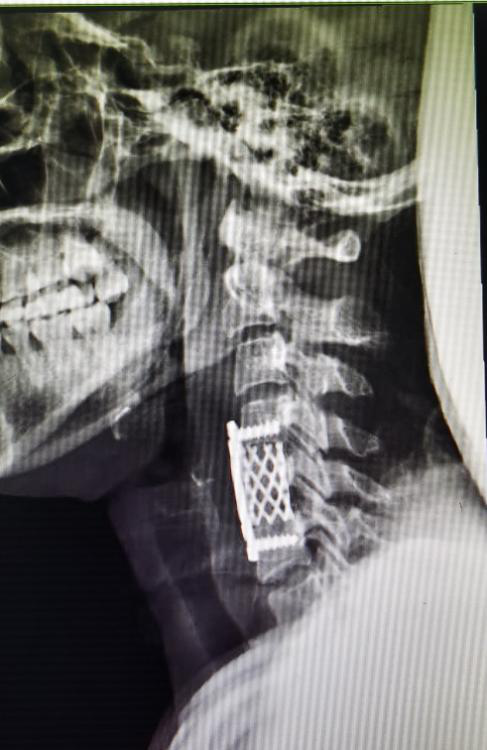

该患者系“右上肢麻木伴左下肢疼痛半年”入院,术前颈椎MR提示C5-6水平脊髓前方囊性占位(图1),囊肿的基底部位于前正中裂至中央管内(图2)。经科室讨论,采用显微镜下颈前经椎体入路脊髓内肠源性囊肿切除术。术后第四天复查磁共振见囊肿全切,无残留(图3),术后颈椎X线片显示内固定位置良好,颈椎曲度理想(图4.5)。术后患者恢复良好,术后第四天患者自己可以下床行走,四肢肌力正常(图6),右上肢麻木稍减退,左下肢疼痛感消失。

图4:颈椎侧位片

图5:颈椎正位片